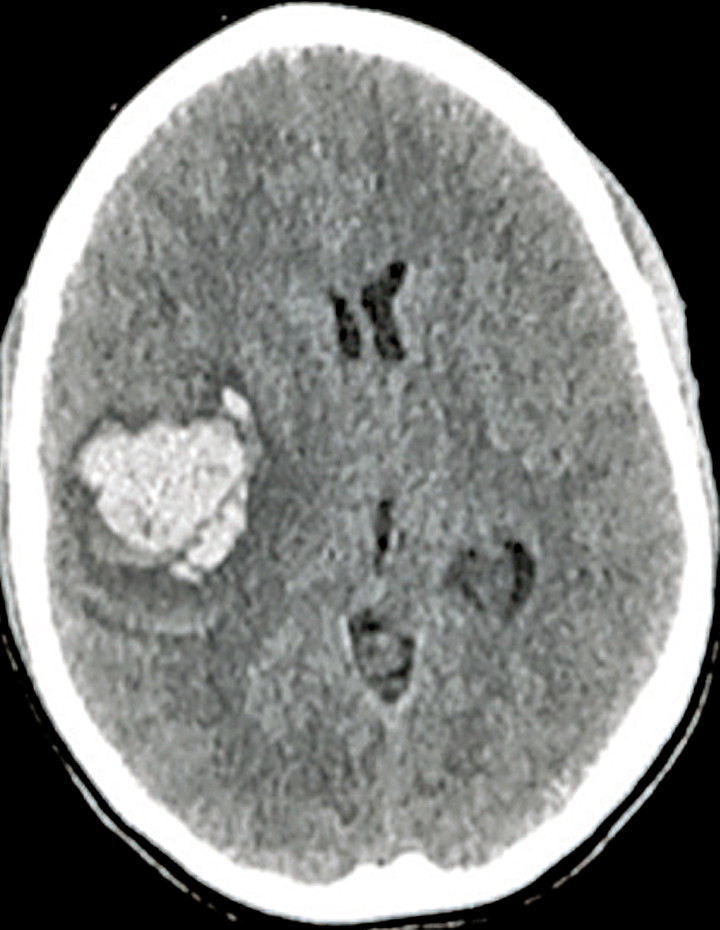

Quel est votre diagnostic ?

Il s'agit d'un hématome intracérébral frontal droit au scanner sans injection. L'hématome intracérébral est une collection de sang consécutive à la rupture d'un vaisseau intracrânien. L'hypertension artérielle est la première cause et l'hémorragie est alors très souvent localisée au niveau des noyaux gris centraux. La deuxième cause est la rupture d'une malformation vasculaire, que ce soit une malformation artérioveineuse, un anévrisme ou un cavernome. Parmi les autres causes, on cite la thrombophlébite cérébrale, les troubles de la coagulation et l'angiopathie amyloïde. Le scanner cérébral, qui est l'examen de référence en cas d'hémorragie cérébrale, met en évidence une plage en hyperdensité et est le plus souvent complété d'un scanner cérébral avec injection et d'un angioscanner cérébral à visée étiologique (recherche de tumeur, de malformation vasculaire, de thrombose veineuse cérébrale). L'IRM cérébrale avec ARM peut être intéressante lorsque le scanner n'est pas contributif pour rechercher une cause de l'hémorragie.